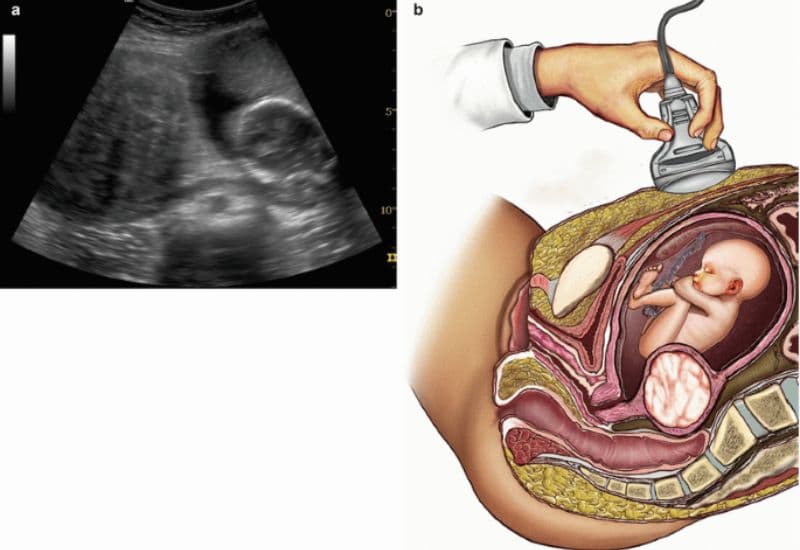

- Thăm khám định kỳ: Việc sàng lọc và khám phụ khoa định kỳ là “chìa khóa” để phát hiện sớm tình trạng cường estrogen và các nhân xơ khi chúng còn nhỏ, giúp việc điều trị dễ dàng và ít tốn kém hơn.